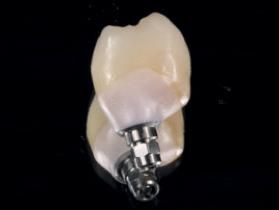

Implant prosthetics and dental prosthetics differ considerably, with the absence of periodontal ligament in the implant/ prosthesis complex. This situation causes mechanical problems to the implants, especially to the implant prosthetic material, due the lack of stress absorption resulting from the normal impact during chewing (1) (2). Among the problems we face in daily practice is the unscrewing and fracturing of veneering material of the implant crown and fracturing of implant/ abutment components.

It is very important to consider that resin based blocks give us the missing part from ceramic materials to solve the problem of anterior exposure. It is also necessary to consider the importance of reliable bonding/union between the resin block and the abutment component of the

implant, because the right transmission of occlusal load depends on the reliability of this bonding interface. One of the biggest advantages of BRILLIANT Crios blocks is the combination with ONE COAT 7 UNIVERSAL, the best bonding system for the resin based blocks according to the scientific literature (3) (4) and also tested in my own practice over the last five years of use.

During daily practice, it is very common to face situations where the implant has to be placed lingually due to normal resorption (Fig. 1) of the buccal plate after the extraction. But, at the same time, it is not necessary to perform bone grafting procedures. The result of this scenario is to increase the stress on the implant-bone complex when we use rigid materials like conventional ceramics (Fig. 2).

For this daily practice situation, the combination of rigid and resilient materials against the antagonist, allows the stress to the implant-bone complex to be reduced (Fig. 3,4).